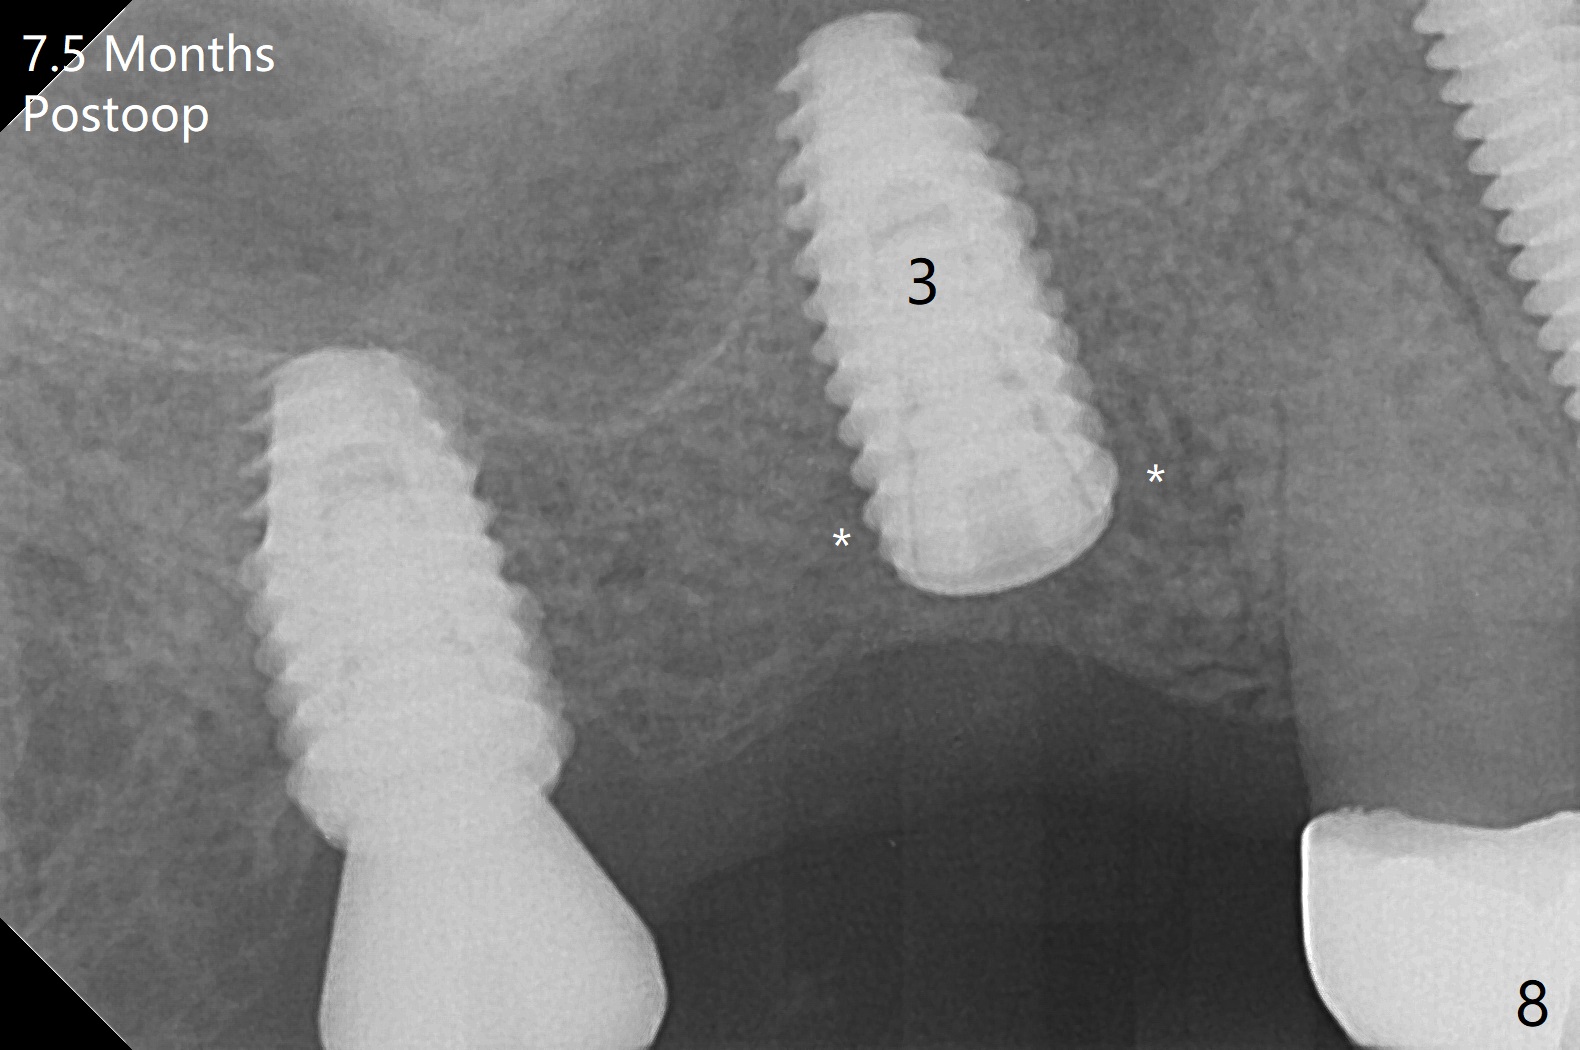

Osteotomy at the sites of #2 and 3 goes on as planned. Sinus lift using DIO 2.8 mm round bur with 6 and 7 mm stoppers (respectively) is carried on without certainty, because it is difficult to feel the stop through the osteotomy. The crest may be uneven or soft. It appears that the soft tissue landmark as a stop may be easier to identify. In fact a 3 mm IBS Magic Expander (an osteotome) was used for sinus lift at #3. The 2 implants are placed with 20 and 30 Ncm (Fig.1,2). Healing abutments are inserted. At 2-week follow-up, the patient reports "pain a few days earlier, took a pill of antibiotic, pain gone. UR metal is sharp". She does not take antibiotic regularly. Exam reveals that there is heavy plaque around #2,3 healing abutments. The buccal edge of #2 abutment is trimmed for comfort. Nearly 1 month postop, #3 healing abutment dislodges with buccal gingival erythema and edema with purulent discharge (Fig.3). Healing screw is placed at #3 with Amoxicillin and Chlorhexidine prescribed. One week later, the implant at #3 turns when the healing screw is retightened (Fig.4). After debridement, Vanilla graft is placed. There is no infection at #2 or 3 four months postop (Fig.5,6); the lingual gingiva is erythematous and edematous at #29 with mobility II (Fig.7 (vertical root fracture)). Uncover is conducted at the site of #3; there is no infection superficial 7.5 months postop (Fig.8). There is a large buccal defect upon incision with dark hemorrhage. In fact the bone density is low crestally (Fig.8 *). Bone graft is placed for the 2nd time. Eleven months later (1.5 years post implant placement), the bone regrows crestal (Fig.9 *). The crown at #3 is loose 1 year 5 months post cementation (Fig.10). After proximal trimming (Fig.11 *), the abutment at #3 is seated completely. After lab repair, crown oral cement, crown/abutment removal for excess cement removal, the crown/abutment cannot be torqued >25 Ncm (Fig.12, 30 Ncm). PA shows incomplete seating (Fig.12 <). Then the crown is sectioned so that the abutment has more freedom to be seated completely with pressure against the gingiva (the patient feels pain, Fig.13). Torque is 30 Ncm. After crown cementation, the abutment will not be removed for cement removal.